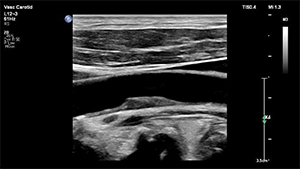

組織をより精密かつ明瞭に表示するため,高分解能画像処理技術XRES Proを搭載した。XRES Proは,複数のパラメトリックフィルターを使用し,画像要素を細分化。これらのデータを解析して,高度なアルゴリズムにより境界の鮮明化,組織の明瞭化を向上することで, 解剖学的構造の描出能が高まる。その結果,血管エコーでは,アーチファクトが低減しプラークの形態などが把握しやすくなり,超音波診断の確信性を高める。